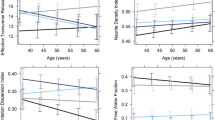

In the hippocampus (Table 2a), there was a significant association between all measures of microstructural integrity and age, suggesting a quadratic relationship (Fig. 2a). ICVF was significantly predicted by age, age2, sex, and BMI (adj. R2 = 0.254, F(9,357) = 14.84, p < 0.001), OD showed a significant association with age, age2, GMV, and sex (adj. R2 = 0.323, F(9,357) = 20.4, p < 0.001), ISOVF was associated with age, age2, and GMV (adj. R2 = 0.549, F(9,357) = 50.46, p < 0.001), and MTR was explained by age and age2 (adj. R2 = 0.405, F(9,354) = 28.41, p < 0.001), explaining between 25 and 55% of variance in hippocampal microstructure. With MTR and ICVF, a non-significant trend (p < 0.10) for the ACE-R score was observed.

The association of a age and b body mass index (BMI) with microstructure of the hippocampus and hypothalamus, assessed by orientation dispersion (n = 369), isotropic volume fraction (n = 369), intracellular volume fraction (n = 369), and magnetization transfer ratio (n = 366). For the regression lines, a quadratic term was used

In the hypothalamus (Table 2b), ICVF displayed a positive correlation with sex and BMI (adj. R2 = 0.118, F(9,357) = 6.422, p < 0.001), OD was negatively related to age2 and BMI (adj. R2 = 0.038, F(9,357) = 2.626, p < 0.005, Fig. 2b), and MTR showed a trend for a negative association with GMV (adj. R2 = 0.078, F(9,354) = 4.404, p < 0.001), explaining between 4 and 12% of variance in hypothalamic microstructure. With ICVF, a non-significant trend for the depression score was observed (p < 0.10). No significant association was found for ISOVF (adj. R2 = 0.022, F(9,357) = 1.897, p = 0.051). See Online Resource Tab.1. And Online Resource Fig. 1 for the predictions of hypothalamic and hippocampal FA and MD. To further investigate whether the influence of BMI on microstructural changes depends on age, we examined the interaction between age and BMI on hypothalamic ICVF, OD, and ISOVF (Online Resource Fig. 2). We found no hint towards a change of this relationship based on age.

In both models, BMI was associated with rs-FC to regions associated with hypothalamic microstructure, suggesting a positive relationship with the hippocampus-amygdala cluster, and a negative relationship with the nucleus accumbens cluster. No significant association was observed for sex or age, but a non-significant trend for a positive correlation of age with nucleus accumbens rs-FC (hippocampus-amygdala connectivity: adj. R2 = 0.065, F(4,358) = 9.333, p < 0.001; nucleus accumbens connectivity: adj. R2 = 0.039, F(4,358) = 5.818, p < 0.001). In other words, we found an additional, albeit small influence of BMI on functional connectivity of the hypothalamus, suggesting a stronger positive functional coupling with the hippocampus and amygdala, and stronger negative coupling with the nucleus accumbens with higher BMI (Fig. 4, Table 3).